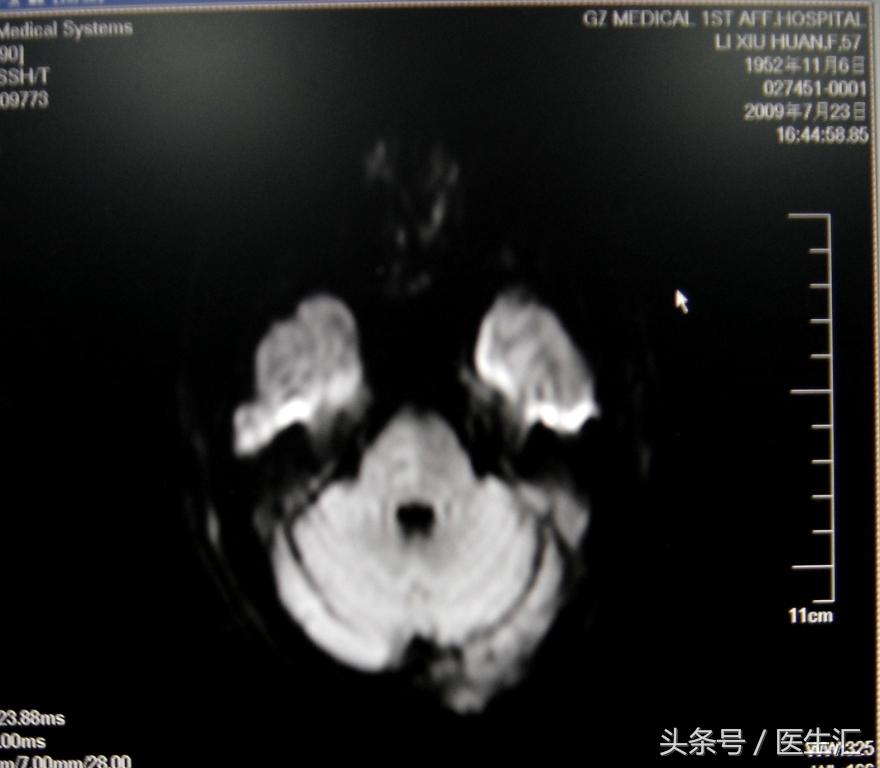

头颅MRI和MRA(图6)

专家判读:桥脑右侧半球后部,丘脑后部为实际梗死灶。大脑后动脉,一侧椎动脉显影不清。